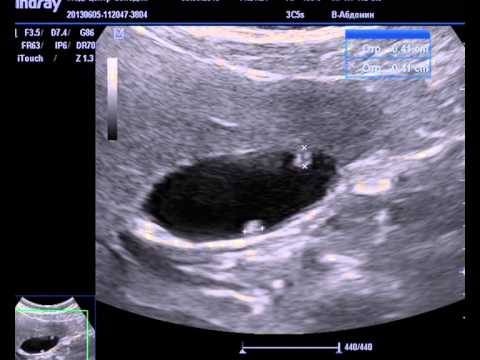

Самой первой назначаемой в таких случаях процедурой является УЗИ органов брюшной полости, которое легко обнаруживает в полости органа эти округлые новообразования. Часто папилломы находят случайно, при проведении УЗИ по другому поводу.